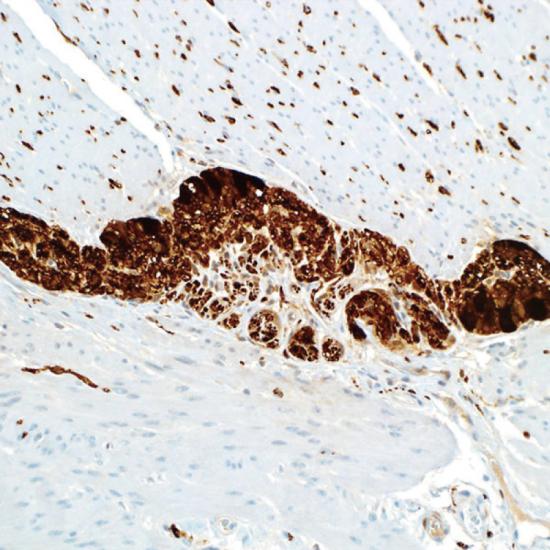

PGP9.5

Protein Gene Product 9.5抗體試劑(免疫組織化學(xué)) 閩廈械備20180215號

• 陽性部位:

細(xì)胞漿/細(xì)胞核

• 陽性對照:

神經(jīng)內(nèi)分泌腫瘤

蛋白基因產(chǎn)物9.5(PGP9.5)是一種神經(jīng)纖維中的特異性泛素羥基水解酶,作為一種神經(jīng)軸突標(biāo)記物,PGR9.5可以與任何無髓或有髓的神經(jīng)纖維相結(jié)合,使用免疫組織化學(xué)的方法即可標(biāo)記出組織中PGP9.5陽性的神經(jīng)纖維。目前PGP9.5主要應(yīng)用于周圍神經(jīng)損傷的臨床研究中。